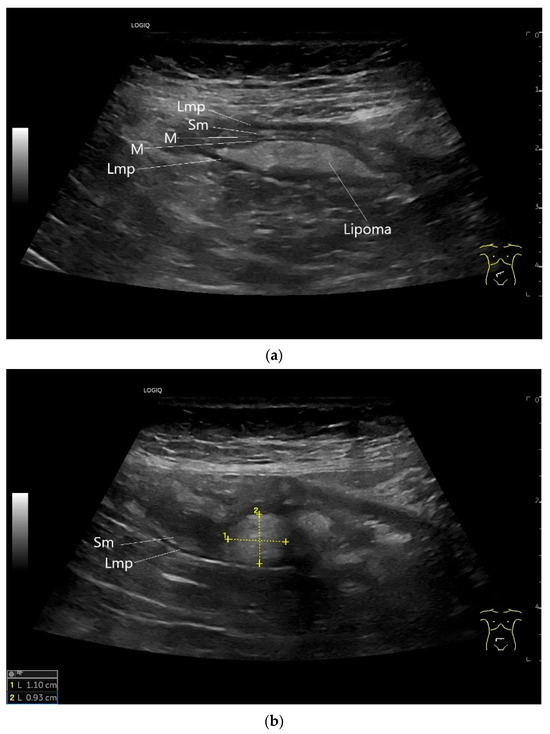

Figure 16.

Lipoma in the ileum. An incidental finding reveals a homogeneous hyperechoic lesion in the right lower abdomen. This can be attributed to the ileum. The mass is shown in longitudinal section (a) and cross-section (b). The longitudinal section (b) shows the layer classification. M—mucosa; Sm—submucosa; Lmp—muscularis propria layer.